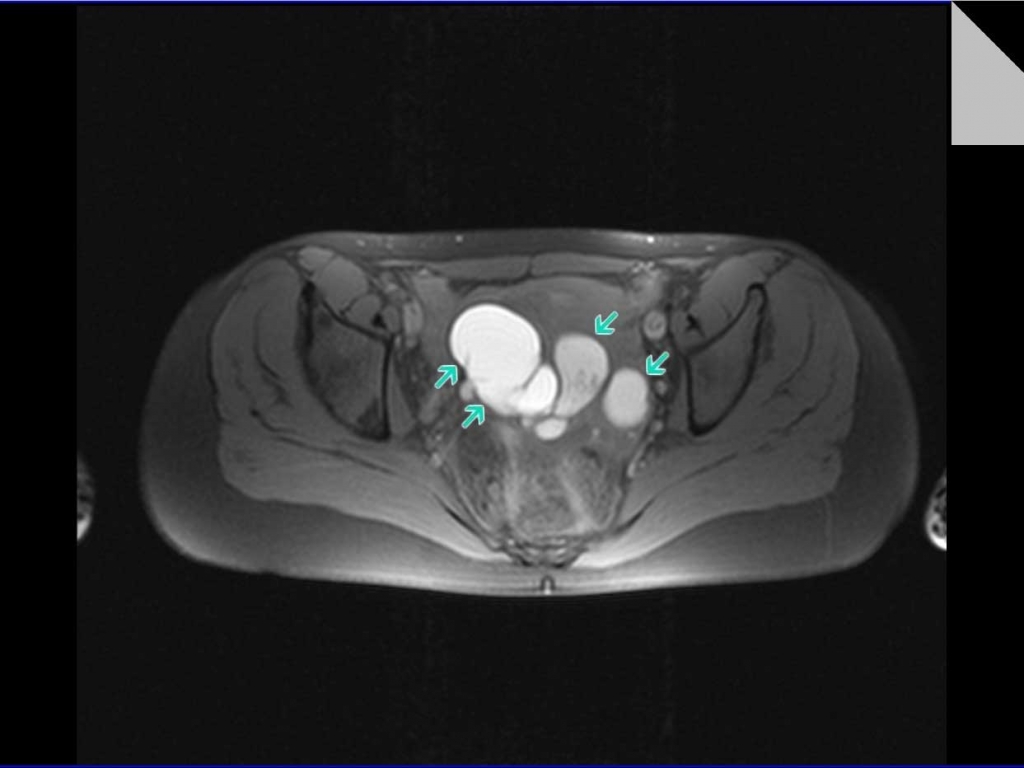

МРТ органов брюшной полости.